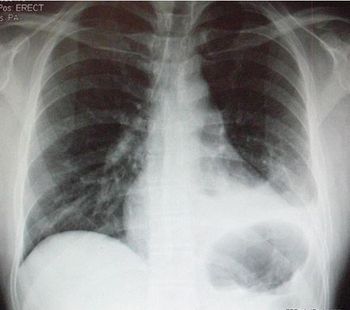

Recovery from a hemopneumothorax had progressed well for this 29-year-old man until today when he presents to the ED with dyspnea and pleuritic chest pain. What do you see on the chest x-ray?